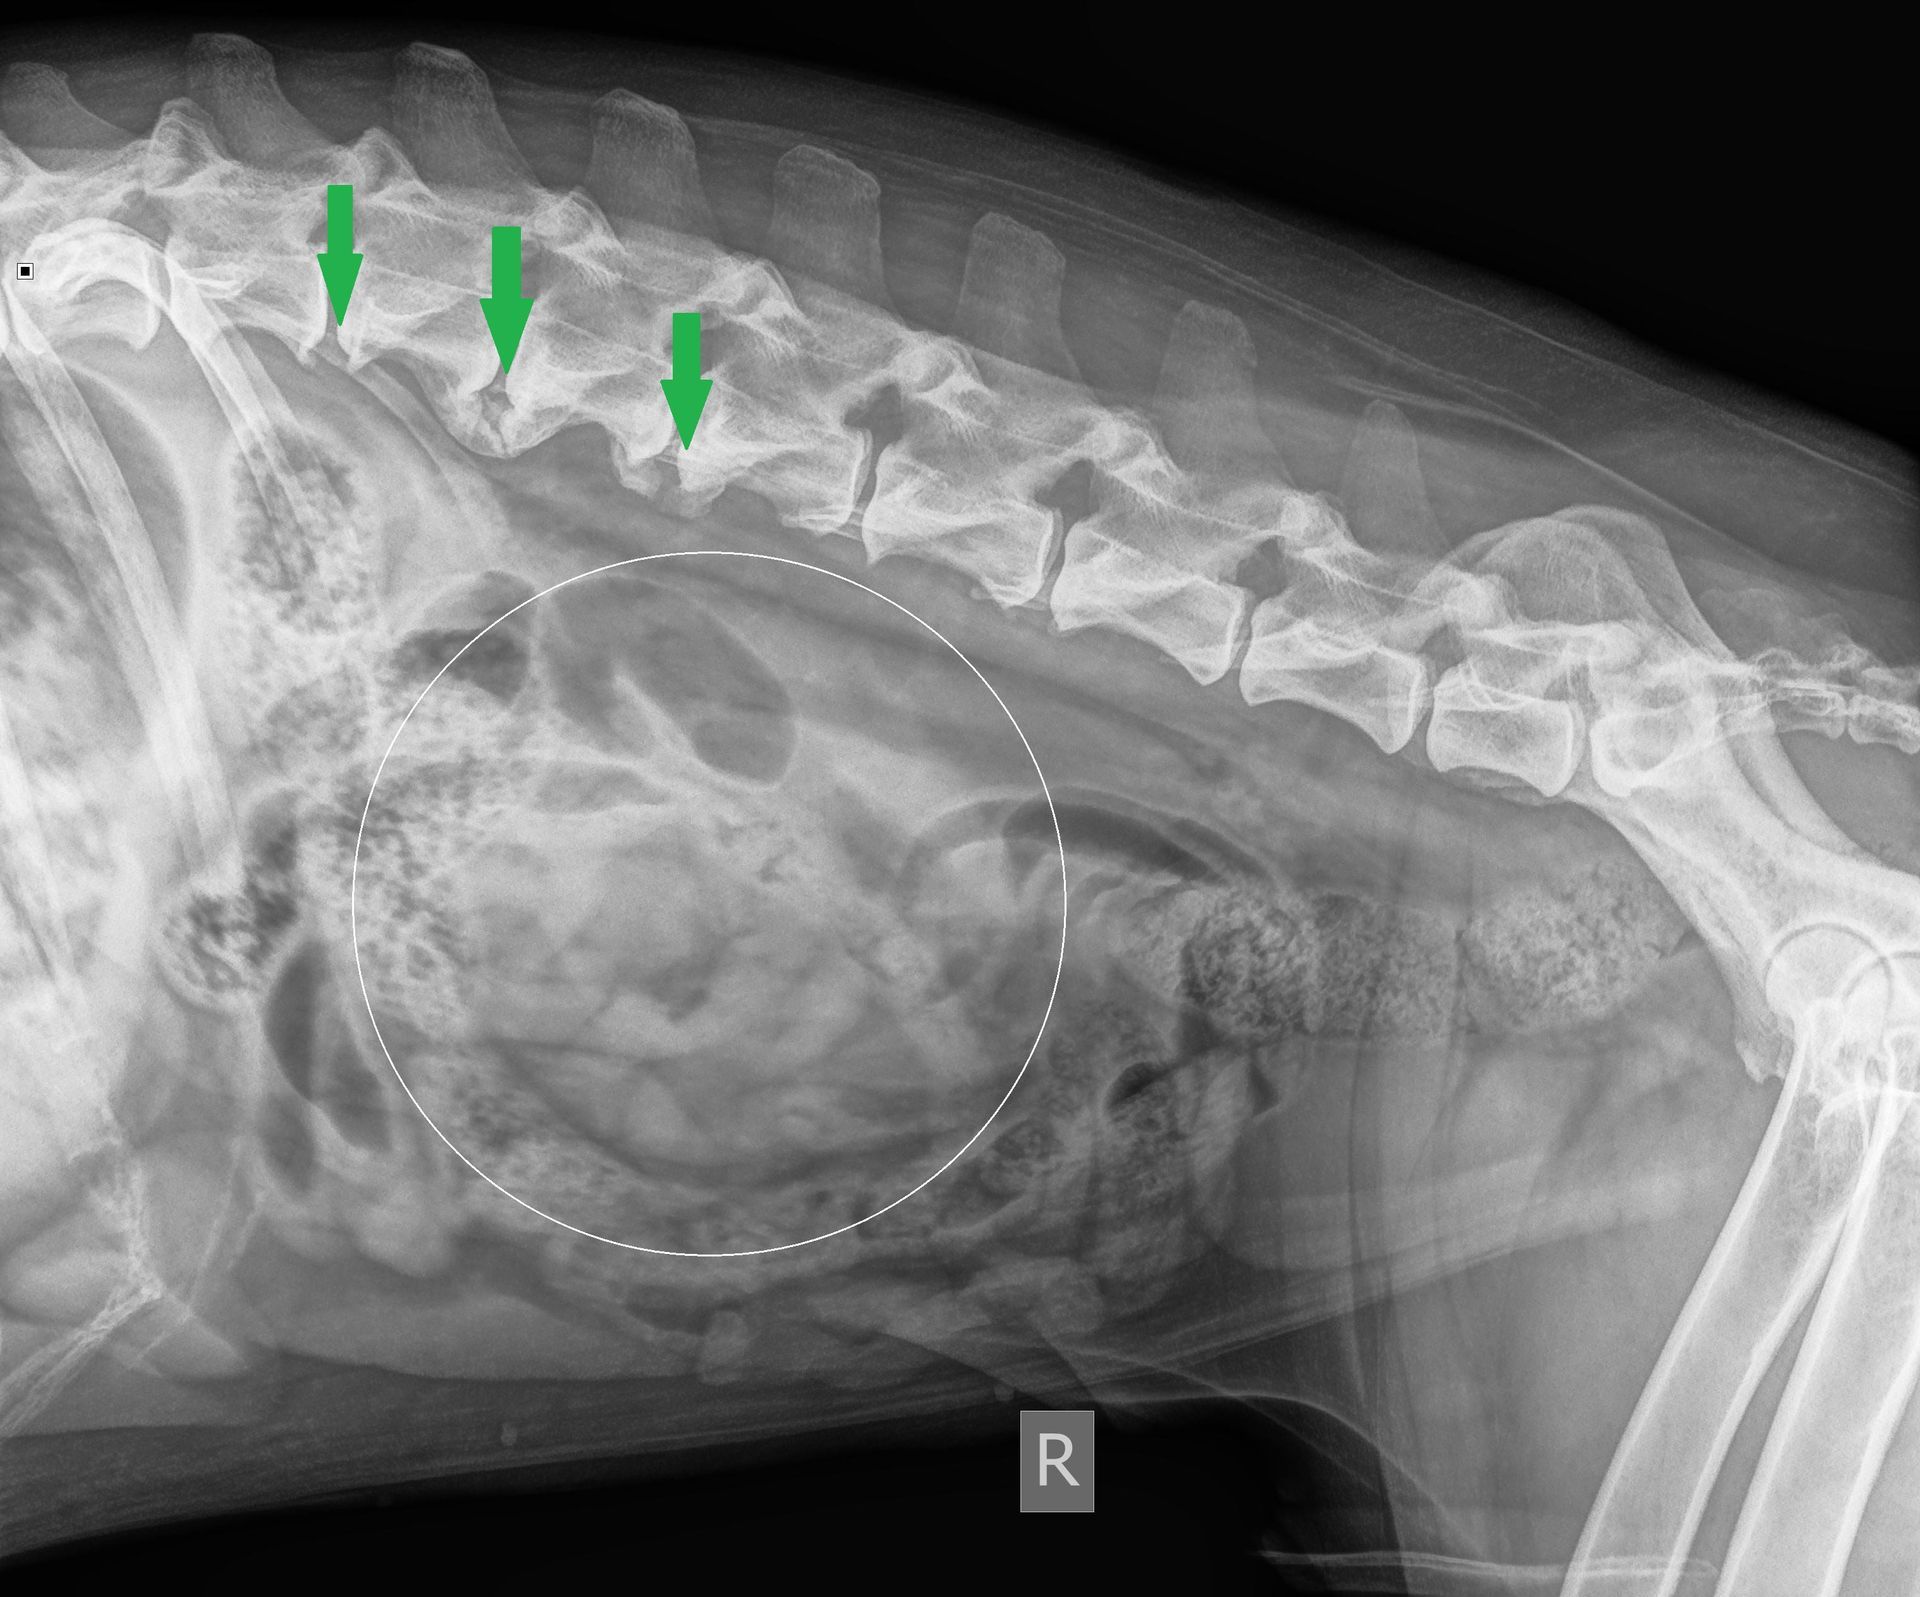

Röntgenbilder

Wir studieren die übermittelten Röntgenbilder. Die Wirbelsäule weist tatsächlich an mehreren Stellen Zeichen einer Rückenarthrose (Spondylose) auf (grüne Pfeile). Im Bauchraum fällt uns ausserdem ein fraglicher Masseneffekt auf: Die Region in der Mitte des Bauches erscheint genüber dem restlichen Bauchraum zu röntgendicht (zu hell), was den Verdacht weckt, dass sich an dieser Stelle Gewebe befindet, welches normalerweise nicht vorhanden ist.

Auch erscheint es seltsam und unüblich, dass die vorhandene Rückenarthrose einen akuten, starken Schmerz verursachen würde. Könnte es sein, dass Maylo stattdessen im Bauchraum ein Problem entwickelt hat?